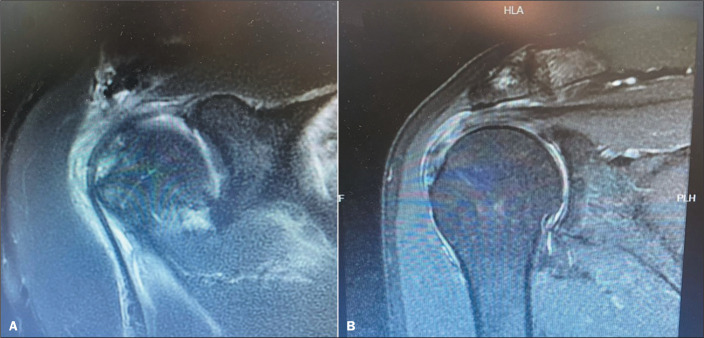

Objective: To evaluate the false-negative rate in the diagnosis of superior labrum anterior to posterior (SLAP) lesions on unenhanced 1.5-T magnetic resonance imaging (MRI).

Materials and methods: This was a retrospective analysis of the medical records of 24 patients who regularly engaged in physical activity and underwent surgery for reconstruction of the rotator cuff or for glenohumeral instability, comparing the result of the MRI examination with the intraoperative findings.

Results: Eighteen patients (75%) were male and six (25%) were female. False-negative results for SLAP lesions were observed in 83% of the MRI examinations.

Conclusion: For SLAP-type lesions, MRI has low diagnostic sensitivity. Arthroscopy appears to be the most efficient tool for the diagnosis of such lesions.